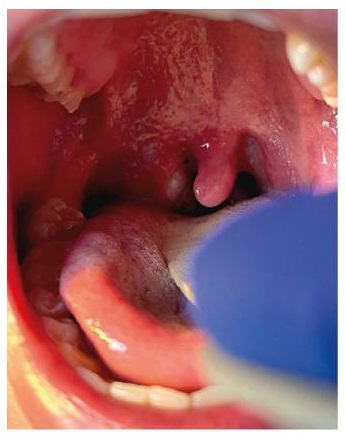

Tonsillar complications were not previously known to be typical. However, they have been reported rarely in the 2022 global clade II mpox outbreak (e.g., tonsillitis, peritonsillar cellulitis, tonsillar/peritonsillar abscess, necrotizing tonsillitis), likely as a consequence of practising oral-receptive sex.[111][200][205][355][356][357] Airway management, antibiotic therapy, and surgery may be required depending on the presentation.

[Figure caption and citation for the preceding image starts]: Right tonsillar enlargement with an overlying pustular lesion and yellow-green exudate with slight deviation of the uvulaBMJ. 2022 Jul 28;378:e072410; CC-BY-NC 4.0 licence [Citation ends].